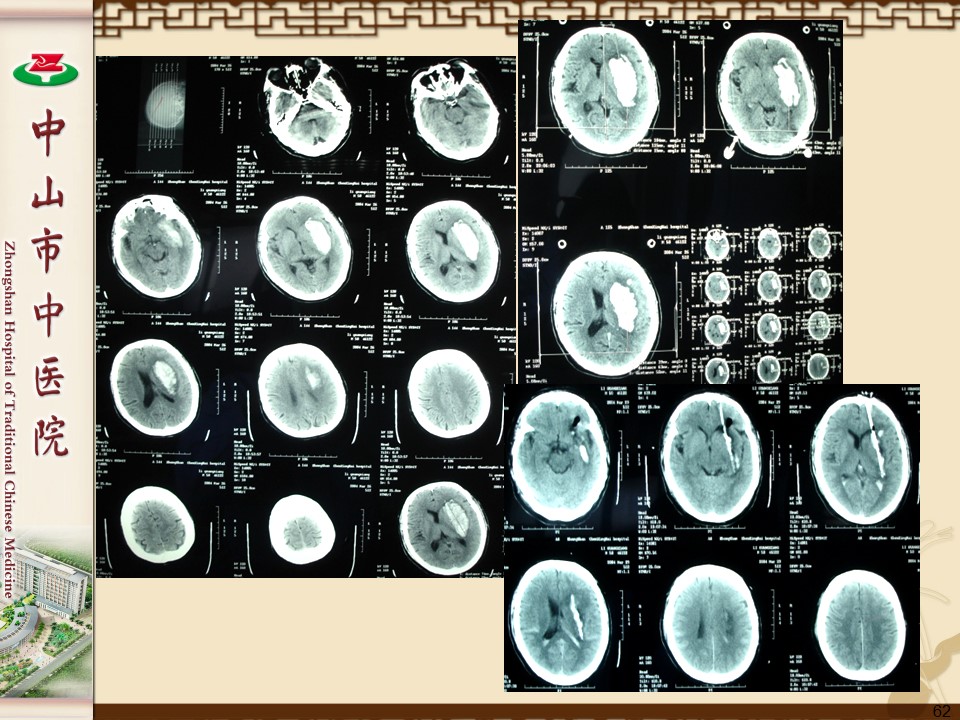

脑出血的外科治疗PPT

高血压脑出血80%在幕上,20%在幕下。常见的出血部位是:

1、壳核出血,约占60%(44%~69%);

2、丘脑出血,约占10%(10%~13%);

3、大脑半球白质出血,约占10%(10%~          26%);

4、脑干出血,约占10%(6%~17%);5、小脑出血,约占10%(4%~13%)。